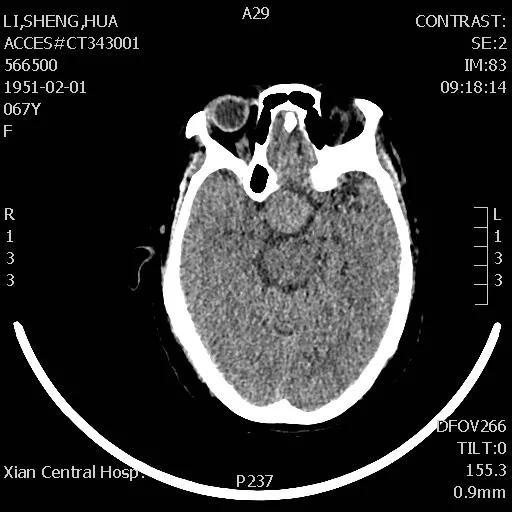

李女士头痛一年多,近日头痛加重并伴有视力迅速下降的症状,经朋友介绍,来到市中心医院神经外科王占尧主任医师处就诊。王主任通过与病人深切交谈,了解其既往病史、生活习惯、家族病史等后,均未发现有何异常,王占尧主任医师立即成立诊疗小组对李女士的情况进行分析并制定了神经内镜下手术的治疗方案。

手术于次日下午进行,整个过程非常顺利,患者预后也非常理想,术后复查CT显示肿瘤切除干净,患者视力改善明显,经过一段时间的后续治疗,患者已痊愈出院。